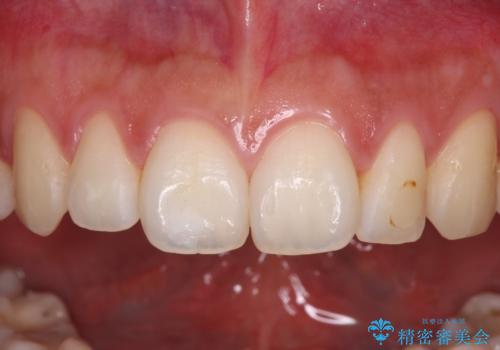

- 前歯に痛みを感じて来院された患者様です。

以前虫歯治療を行った歯が痛み出し、鼻の下を押すと強い痛みを感じていました。

レントゲン写真から、大きくなった根尖病変が認められました。

根管治療を行い、その後オールセラミッククラウンにて補綴治療を行うこととしました。